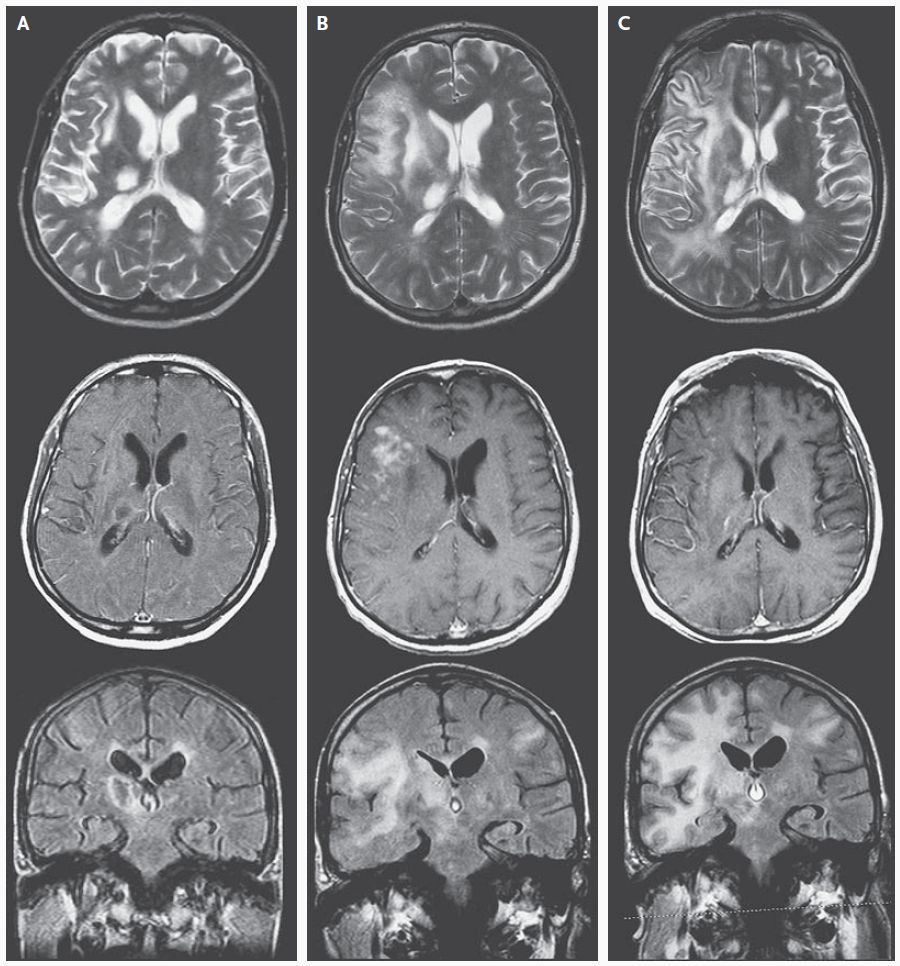

Fazekas grades. Мультифокальная лейкоэнцефалопатия. Резидуальная энцефалопатия на мрт. Прогрессирующая мультифокальная лейкоэнцефалопатия кт. Гипертензионная энцефалопатия на мрт.

Fazekas grades. Мультифокальная лейкоэнцефалопатия. Резидуальная энцефалопатия на мрт. Прогрессирующая мультифокальная лейкоэнцефалопатия кт. Гипертензионная энцефалопатия на мрт.

Fazekas grades. Brain MRI. Wilson Brain MRI. Фазекас классификация мрт. Лейкоареоз Фазекас.

Fazekas grades. Brain MRI. Wilson Brain MRI. Фазекас классификация мрт. Лейкоареоз Фазекас.